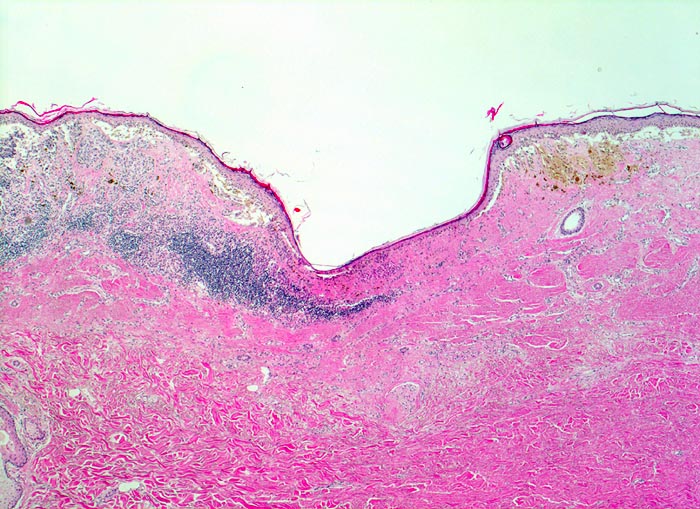

Malignes Melanom

Haut, untere Extremität

Asymmetrischer, in der oberen Dermis gelegener, teils pigmentierter Tumor mit begleitendem perifokalem Entzündungsinfiltrat. Fokal fehlen Tumorzellen (Regression). Anstelle der Tumorzellen narbenartige Fibrose und Entzündungszellen.

Stellenweise erhabene, unregelmässig begrenzte und inhomogen gefärbte braun-schwarze Hautläsion.

Rasch gewachsene Hautläsion am Unterschenkel.

Der oberflächliche Anteil maligner Melanome zeigt oft Zeichen der Regression. Die Zerstörung der Tumorzellen durch das körpereigene Immunsystem hinterlässt in der papillären Dermis eine narbenartige Fibrosezone, Gefässneubildungen und Melanophagen. Bei vollständiger Regression eines malignen Melanoms kann es vorkommen, dass trotz metastasierendem Tumorleiden kein Primärtumor gefunden wird.